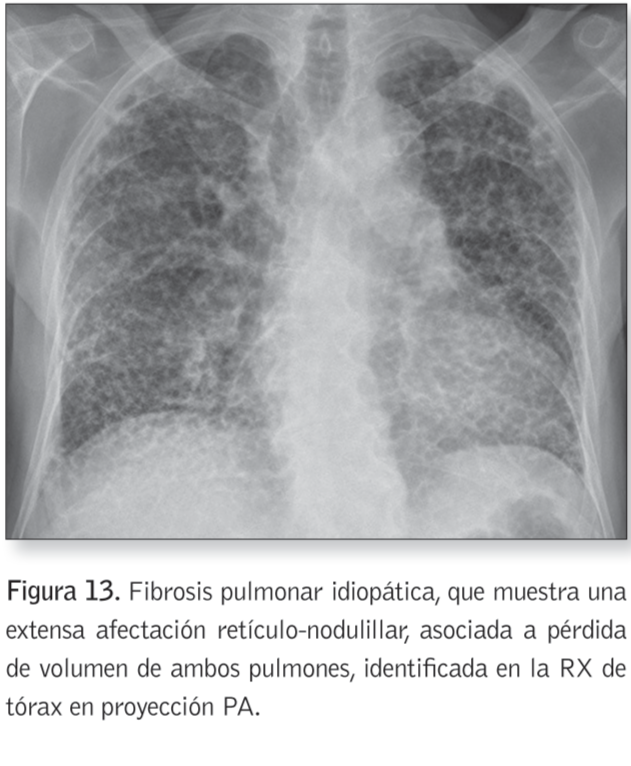

Patrón reticulo-nodulillar